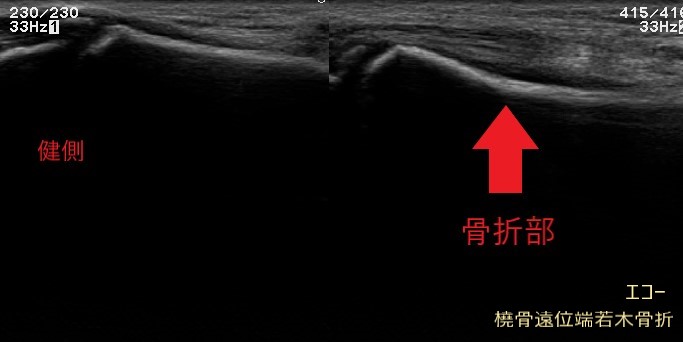

超音波(エコ-)検査は、骨・靭帯・筋肉・腱などの病態を診る検査装置です。

関節や筋肉を実際に動かしつつ観察できるため、状態の変化や回復の様子を把握しながら進めていきます。

レントゲン画像には映りにくい筋肉や腱、靭帯などの状態に加え、骨の様子もあわせて確認できます。